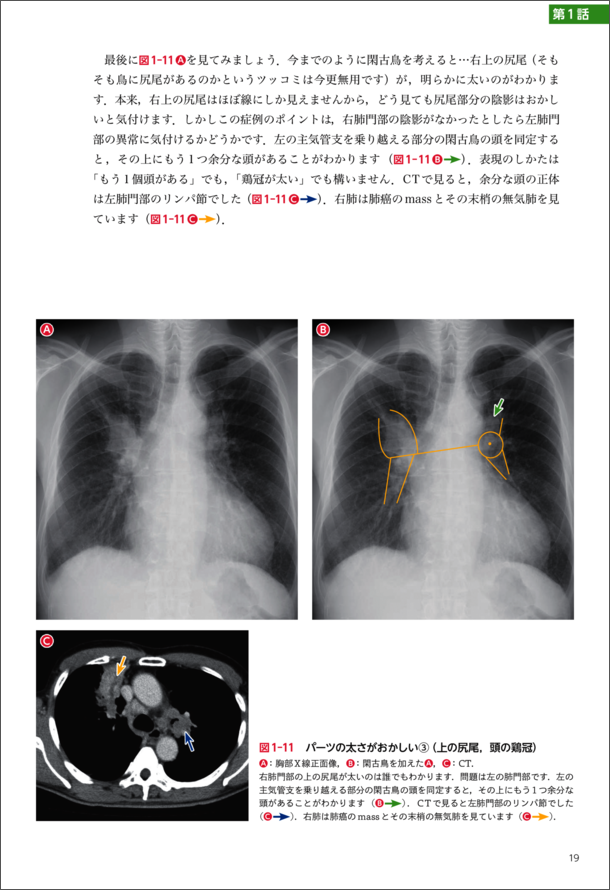

『第1話 肺門編「閑古鳥を探せ!」』より抜粋